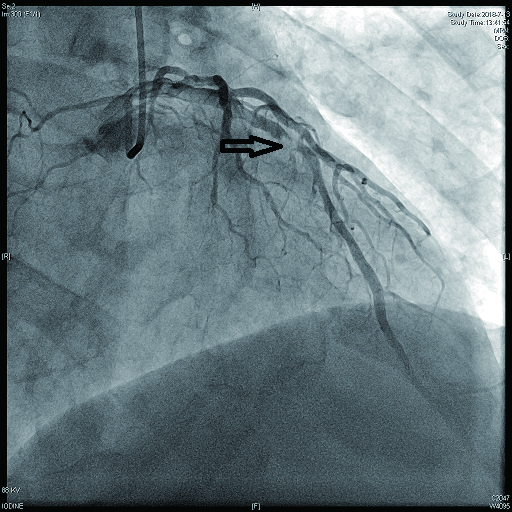

2 结果 本研究收集7例De winter综合征患者,6例进行了急诊冠脉造影,胸痛至球囊扩张平均时间为3.3 h,1例进行择期冠脉造影。其中,3例为前降支近段严重病变,1例为第一对角支闭塞,3例为前降支中段闭塞,2例合并多支血管病变,5例为单支血管病变,均行前降支支架植入术(表 4)。1周内行心脏彩超检查,4例出现室壁运动减弱,2例EF值小于50%,2例心脏形态结构未见异常,1例患者术后第2天因个人原因自动出院,未完善心脏彩超(表 5)。观察7例患者住院期间心电图演变情况,其中有3例在PCI术后出现前壁导联ST段抬高,4例未出现ST段抬高(表 5)。病例1住院期间出现室性心动过速,病例7患在急诊科就诊时发生呼吸心搏骤停,经抢救后送导管室行急诊冠脉造影。另外,所有患者经药物及介入治疗后,均症状缓解出院,院外长期服用阿司匹林100 mg/d+替格瑞洛90 mg/12 h+阿托伐他汀40 mg/瑞舒伐他汀20 mg等药物,出院1个月后电话随访,7例患者均无胸痛、气促发作及再住院,无死亡病例。

表 4 7例患者冠脉造影及介入治疗情况

| 编号 |

是否急诊冠脉造影 |

冠脉造影结果 |

介入治疗情况 |

| 病变血管支数 |

罪犯血管 |

罪犯血管狭窄程度 |

罪犯血管TIMI血流 |

| 病例1 |

是 |

1 |

LAD近段(图 9) |

75%~90% |

2级 |

LAD近段植入支架1枚 |

| 病例2 |

是 |

3(图 6~8) |

LAD近段 |

次全闭塞 |

2级 |

LAD近段植入支架1枚 |

| 注:LAD为左冠状动脉前降支; TIMI为心肌梗死溶栓治疗 |

表 5 7例患者的心电图演变及心脏彩超结果

| 编号 |

心电图是否演变为ST段抬高 |

心脏彩超 |

| 病例1 |

是(图 3~5) |

左心扩大,左室前间壁、前侧壁及心尖部运动减弱,EF 35% |

否(图 1~2) |

心脏形态结构未见异常,EF 56% |